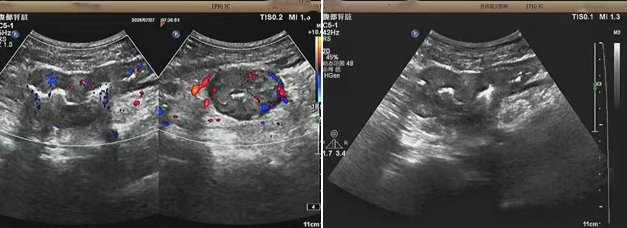

超聲檢查的結(jié)果進(jìn)一步揭示了病情的細(xì)節(jié):下腹部偏左腸壁顯著增厚,原本清晰的層次結(jié)構(gòu)遭到破壞,周圍脂肪間隙變得模糊,網(wǎng)膜回聲也出現(xiàn)增強(qiáng)的現(xiàn)象,同時(shí),腸腔狹窄的情況也得到了確認(rèn)。經(jīng)過(guò)完善的檢查,最終將病變精準(zhǔn)定位在乙狀結(jié)腸 - 直腸交界區(qū),并且對(duì)病變范圍及周圍浸潤(rùn)情況做出了評(píng)估,這些關(guān)鍵信息為后續(xù)的診療工作提供了重要依據(jù),讓醫(yī)生們能更有針對(duì)性地制定治療方案。

我院超聲檢查在此次診療過(guò)程中展現(xiàn)出了顯著的技術(shù)亮點(diǎn)。一方面,它能做到 “明察秋毫”,通過(guò)高頻探頭可以清晰地顯示腸壁各層結(jié)構(gòu)的變化,為臨床判斷病變性質(zhì)提供了客觀、準(zhǔn)確的依據(jù),讓醫(yī)生能更清晰地了解腸道內(nèi)部的病變狀態(tài)。另一方面,它實(shí)現(xiàn)了 “精準(zhǔn)評(píng)估”,不僅準(zhǔn)確找到了病變的位置,還能全面評(píng)估病變對(duì)周圍組織的影響,這對(duì)于協(xié)助醫(yī)生制定科學(xué)合理的治療方案起到了至關(guān)重要的作用,有助于提高治療的有效性和安全性。